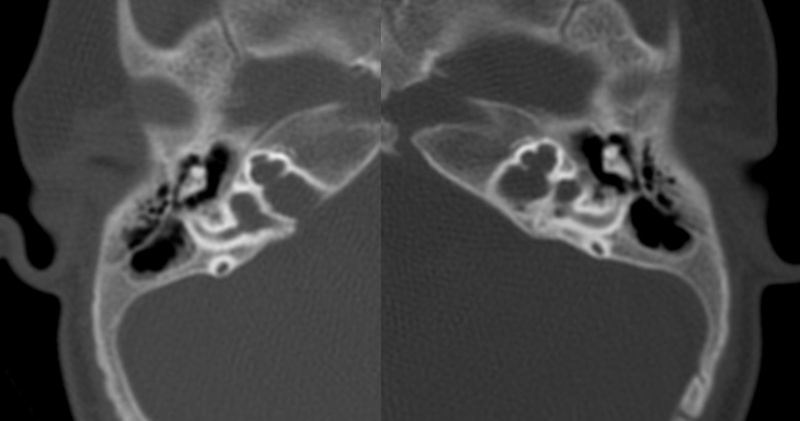

Evaluación de Imagen (TC)

Los hallazgos radiológicos, mediante TC de oídos a cuatro pacientes varones y una madre oyente, portadora obligada, se analizaron y clasificaron según Sennanoğlu et al. [8,9]. En ese sentido, son consistentes con PI-III en tres de ellos: IV-1, IV -2 y IV- 4. El paciente IV-3 mostró PI-I; la madre portadora obligada no mostró alteración alguna (Ver Tabla 3). En los cuatro pacientes estudiados de esta familia observamos dos tipos de MOI, PI-I y PI-III, incluso entre los hermanos IV-2 y IV-3, que presentaron diferente tipo de PI, lo que evidencia expresividad variable. La malformación PI-III es de las MOI menos frecuente y se encuentra presente en este estudio familiar como predominante.

Imagen 8

Corte axial de TC de ambos oídos del paciente IV-2 con PI tipo III.